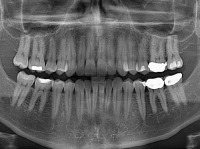

به گزارش ایسنا به نقل از پاپیولارساینس، دندانپزشکان سالانه صدها میلیون پوسیدگی دندان را با خالی کردن دندان و پر کردن آن درمان میکنند.

اما در این میان، 10 تا 15 درصد درمان مذکور ناموفق بوده که منجر به میلیونها مورد عصبکشی و خارج کردن پالپ دندان - بافت نرم مرکز دندان که رگهای خونی، عصبی و بافت مرتبط در آن قرار دارد- میشود.

عصبکشی میتواند به سست شدن دندان منجر شود و در نهایت باید آن دندان را کشید.

محققان نوعی ماده پرکننده دندان از یک ماده زیستی مصنوعی درست کردهاند که میتواند رشد سلولهای بنیادی را در پالپ دندان تحریک کند. این پرکننده مانند انواع معمولی در دندان تزریق شده و با نور فرابنفش جامد میشود.